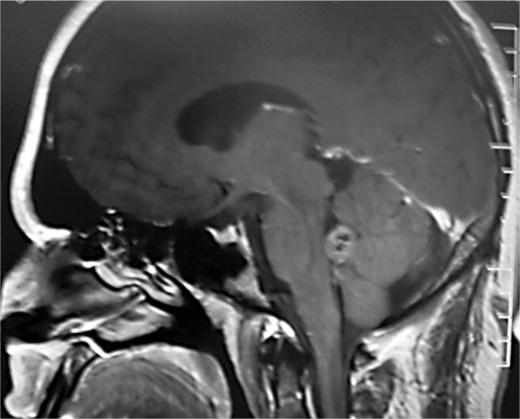

A rare case of subependymoma in a young patient presenting with sensory dysesthesia is reported. Computed tomography scan and magnetic resonance imaging revealed a posterior fossa mass occluding the fourth ventricle with infiltration to the right side immediately behind the pontine tegmentum and impinging on the right spinothalamic tract. Postoperative tumor histopathology revealed the classical appearance of subependymoma. Subependymoma is a rare, asymptomatic, slow-growing, low-grade glioma of the central nervous system. If symptomatic, the clinical features are commonly secondary to hydrocephalus, but subependymoma presenting with sensory dysesthesia has never been reported in the literature.